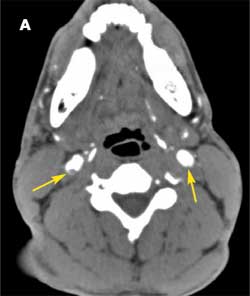

A 37-year-old man was brought to the emergency department (ED) after he had 2 near-syncopal events. The first occurred in the morning and rapidly resolved; the second occurred later in the day at work. The night before he had a headache and neck pain. In the ED, he reported left arm and leg weakness and was noted to have left facial droop.